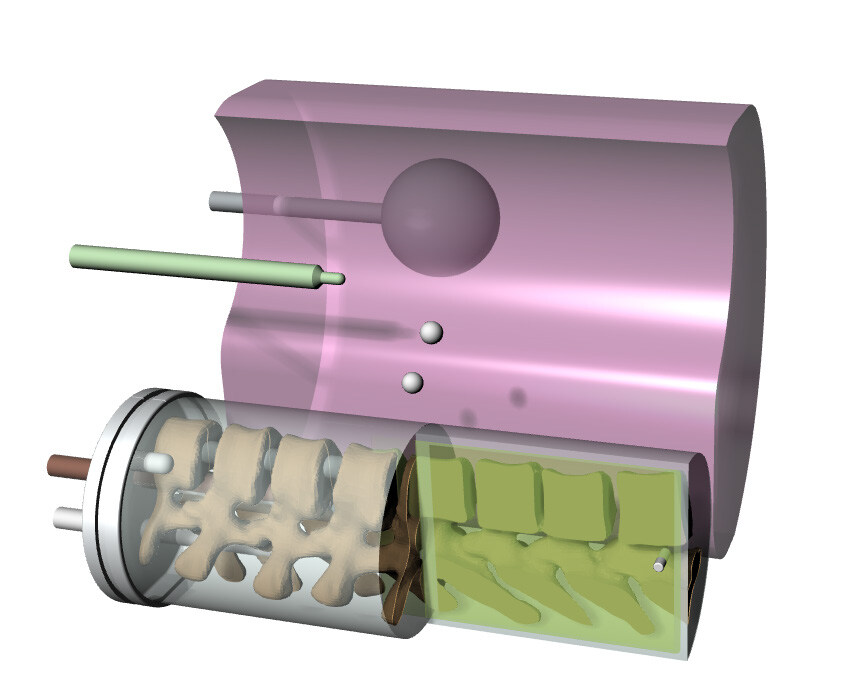

The End-to-End SBRT Phantom is a single tool for high-accuracy end-to-end commissioning and routine QA necessary for the high dose per fraction associated with SBRT deliveries.

Linear attenuations of the simulated tissues are within 1% of actual attenuation for water and bone, and within 3% for lung from 50 keV to 15 MeV. The phantom contains a 3D anthropomorphic removable spine with cortical and trabecular bone as internal landmarks

The E2E SBRT Phantom contains multiple targets and alignment marks for verifying that imaging, localization, and targeting systems are aligned. This is a critical need for accurate delivery of these high-dose treatments.

Three OSL pockets in the right lung provide high-resolution dosimetry measurements to the target and spinal cord in a single delivery.

The removable split spine allows for film measurements in the sagittal orientation in the inferior half of the spine rod. Film can also be placed in the sagittal slice in the spine and lung inserts.